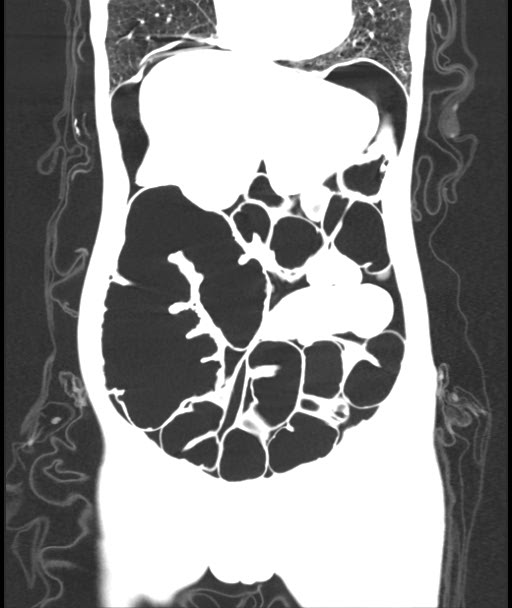

CECT Abdomen: F/S/O Acute Intestinal Obstruction (transition point in transverse colon) with minimal free fluid in pelvis with pneumoperitonium with few air foci in the wall of ascending colon Pneumatosis intestinalis

Cause Midgut volvulus

Adhesion Band

Figure 2: Cect Showing Features of Intestinal Obstruction

Radiologic imaging may be abnormal and detect CV in 45–56% of the cases [5] .Plain abdominal x-ray is highly sensitive for the diagnosis of CV with the characteristic “coffee bean“ sign deformity, its apex pointing to the left upper quadrant [9]. Other findings commonly seen are cecal dilatation (98−100%), single air–fluid level (72–88%), small bowel dilatation (42–55%), and absence of gas in the distal colon (82%). CT is more sensitive and specific for diagnosing CV and detecting complications [10].